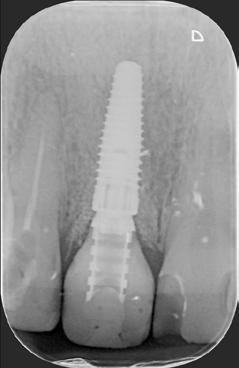

12. kép: A 6 hónapos intraorális kontrollröntgen felvétele.

A 2020 januárjában elkezdett kezeléssorozat befejezését az év márciusában, hazánkba is begyűrűző Covid-19 pandémia késleltette, így kb. 6 hónap gyógyulás után láttunk hozzá az emergencia profil és a gingivális zenit ideiglenes koronával történő formázásához (11. és 12. kép). A 3 hetente végzett apró alakításokkal sikerült megfelelő ínyprofilt kialakítani, a „rózsaszín esztétika” a páciens számára is megfelelő volt. A bal felső nagymetsző fog meziális kompozit tömés cseréjét követően, individualizált nyitott kanalas lenyomati fejet készítettünk: az akrilát ideiglenes korona profilját átlátszó szilikonnal lemásoltuk, majd a körszimmetrikus gyári lenyomati fej és az ideiglenes korona kontúrja közötti hézagot folyékony kompozittal töltöttük ki (13. kép). Az így készített egyéni lenyomati fejjel vettünk lenyomatot a végleges, kerámialeplezésű cirkónium-dioxid vázas, átmenő csavaros rögzítésű koronához. (A fogtechnikai munkát Nébl Péter fogtechnikusmester készítette.), (14., 15., 16 és 17. képek).

A kész korona átadásakor a páciens elégedett volt az esztétikával, az azóta eltelt évben rendszeres kontrollokon jelent meg, melyek során meggyőződtünk a kemény- és lágyszövetek stabilitásáról (18. és 19. képek).